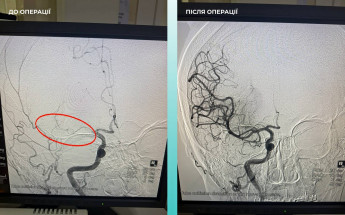

Жительку Одеси доставили до медзакладу у важкому стані з ознаками гострого порушення мозкового кровообігу. Під час комп’ютерної томографії фахівці виявили оклюзію середньої мозкової артерії.

З огляду на критичний стан жінки, мультидисциплінарна команда медиків ухвалила відповідальне рішення — провести одночасну тромбектомію з мозкової та легеневої артерій.

Оперативне втручання минуло успішно. Стан пацієнтки значно покращився: вона при свідомості, з’явилися активні рухи в кінцівках.